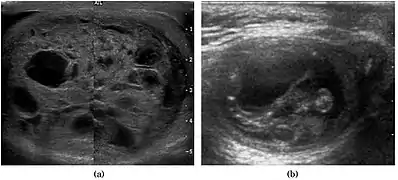

Fig. 3. Seminoma. (a) Seminoma usually presents as a homogeneous hypoechoic nodule confined within the tunica albuginea. (b) Sonography shows a large heterogeneous mass occupying nearly the whole testis but still confined within the tunica albuginea, it is rare for seminoma to invade to peritesticular structures.

Seminoma is the most common tumor type in cryptorchid testes. The risk of developing a seminoma is increased in patients with cryptorchidism, even after orchiopexy. There is an increased incidence of malignancy developing in the contralateral testis too, hence sonography is sometimes used to screen for an occult tumor in the remaining testis. On US images, seminomas are generally uniformly hypoechoic, larger tumors may be more heterogeneous [Fig. 3]. Seminomas are usually confined by the tunica albuginea and rarely extend to peritesticular structures. Lymphatic spread to retroperitoneal lymph nodes and hematogenous metastases to lung, brain, or both are evident in about 25% of patients at the time of presentation.